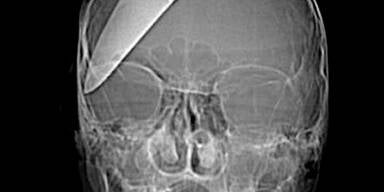

Es ist ein Wunder: Ein 16-jähriger Brite überlebte einen brutalen Angriff - ihm wurde ein Küchenmesser in den Kopf gerammt.

Einem 16-jährigen Teenager wurde ein fast 13 cm langes Küchenmesser in den Schädel gerammt, als er an einer Londoner Bushaltestelle einen Raubüberfall auf einen Bekannten verhindern wollte. Der junge Mann schritt zusammen mit zwei Kameraden beherzt ein - und wurde von den Dieben mit dem Messer attackiert. Ihm rammten sie das Messer in den Schädel, der zweite Bekannte erlitt eine Rückenverletzung, der Dritte wurde an der Schulter getroffen.

Der junge Mann überlebte die schwere Kopfverletzung nur, weil er sofort in ein Spital eingeliefert und einer Notoperation unterzogen wurde. Zehn Monate wurde er entlassen, und besuchte wieder die Schule.